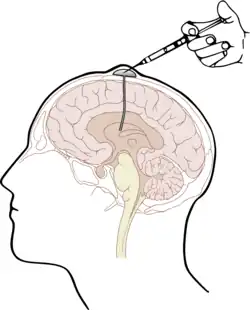

El dispositivo se implanta por medio de cirugía debajo del cuero cabelludo del paciente. El cirujano taladra un orificio mediante un buril en el cráneo a nivel del lóbulo frontal del cerebro e introduce el catéter del dispositivo a través del lóbulo del paciente en el ventrículo cerebral lateral. El depósito del dispositivo queda entonces situado encima del orificio del buril, por debajo de un colgajo de piel cabelluda; los fármacos se administran por inyección en el depósito.